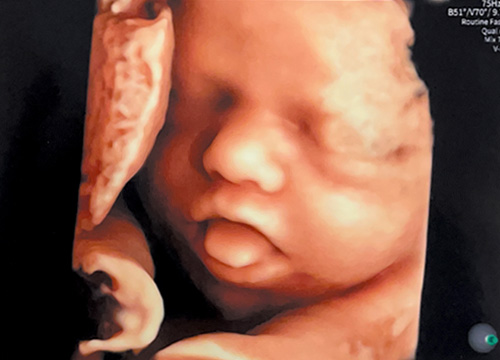

02 《 最新式のGE超音波(Expert22)を導入 》

周産期センターでも導入しているGE製の最新式上位機種を導入しております。とてもきれいな画像で細かい赤ちゃんの仕草がみることができます。患者さんからも従来の機種よりよく見えるとご好評をいただいております。